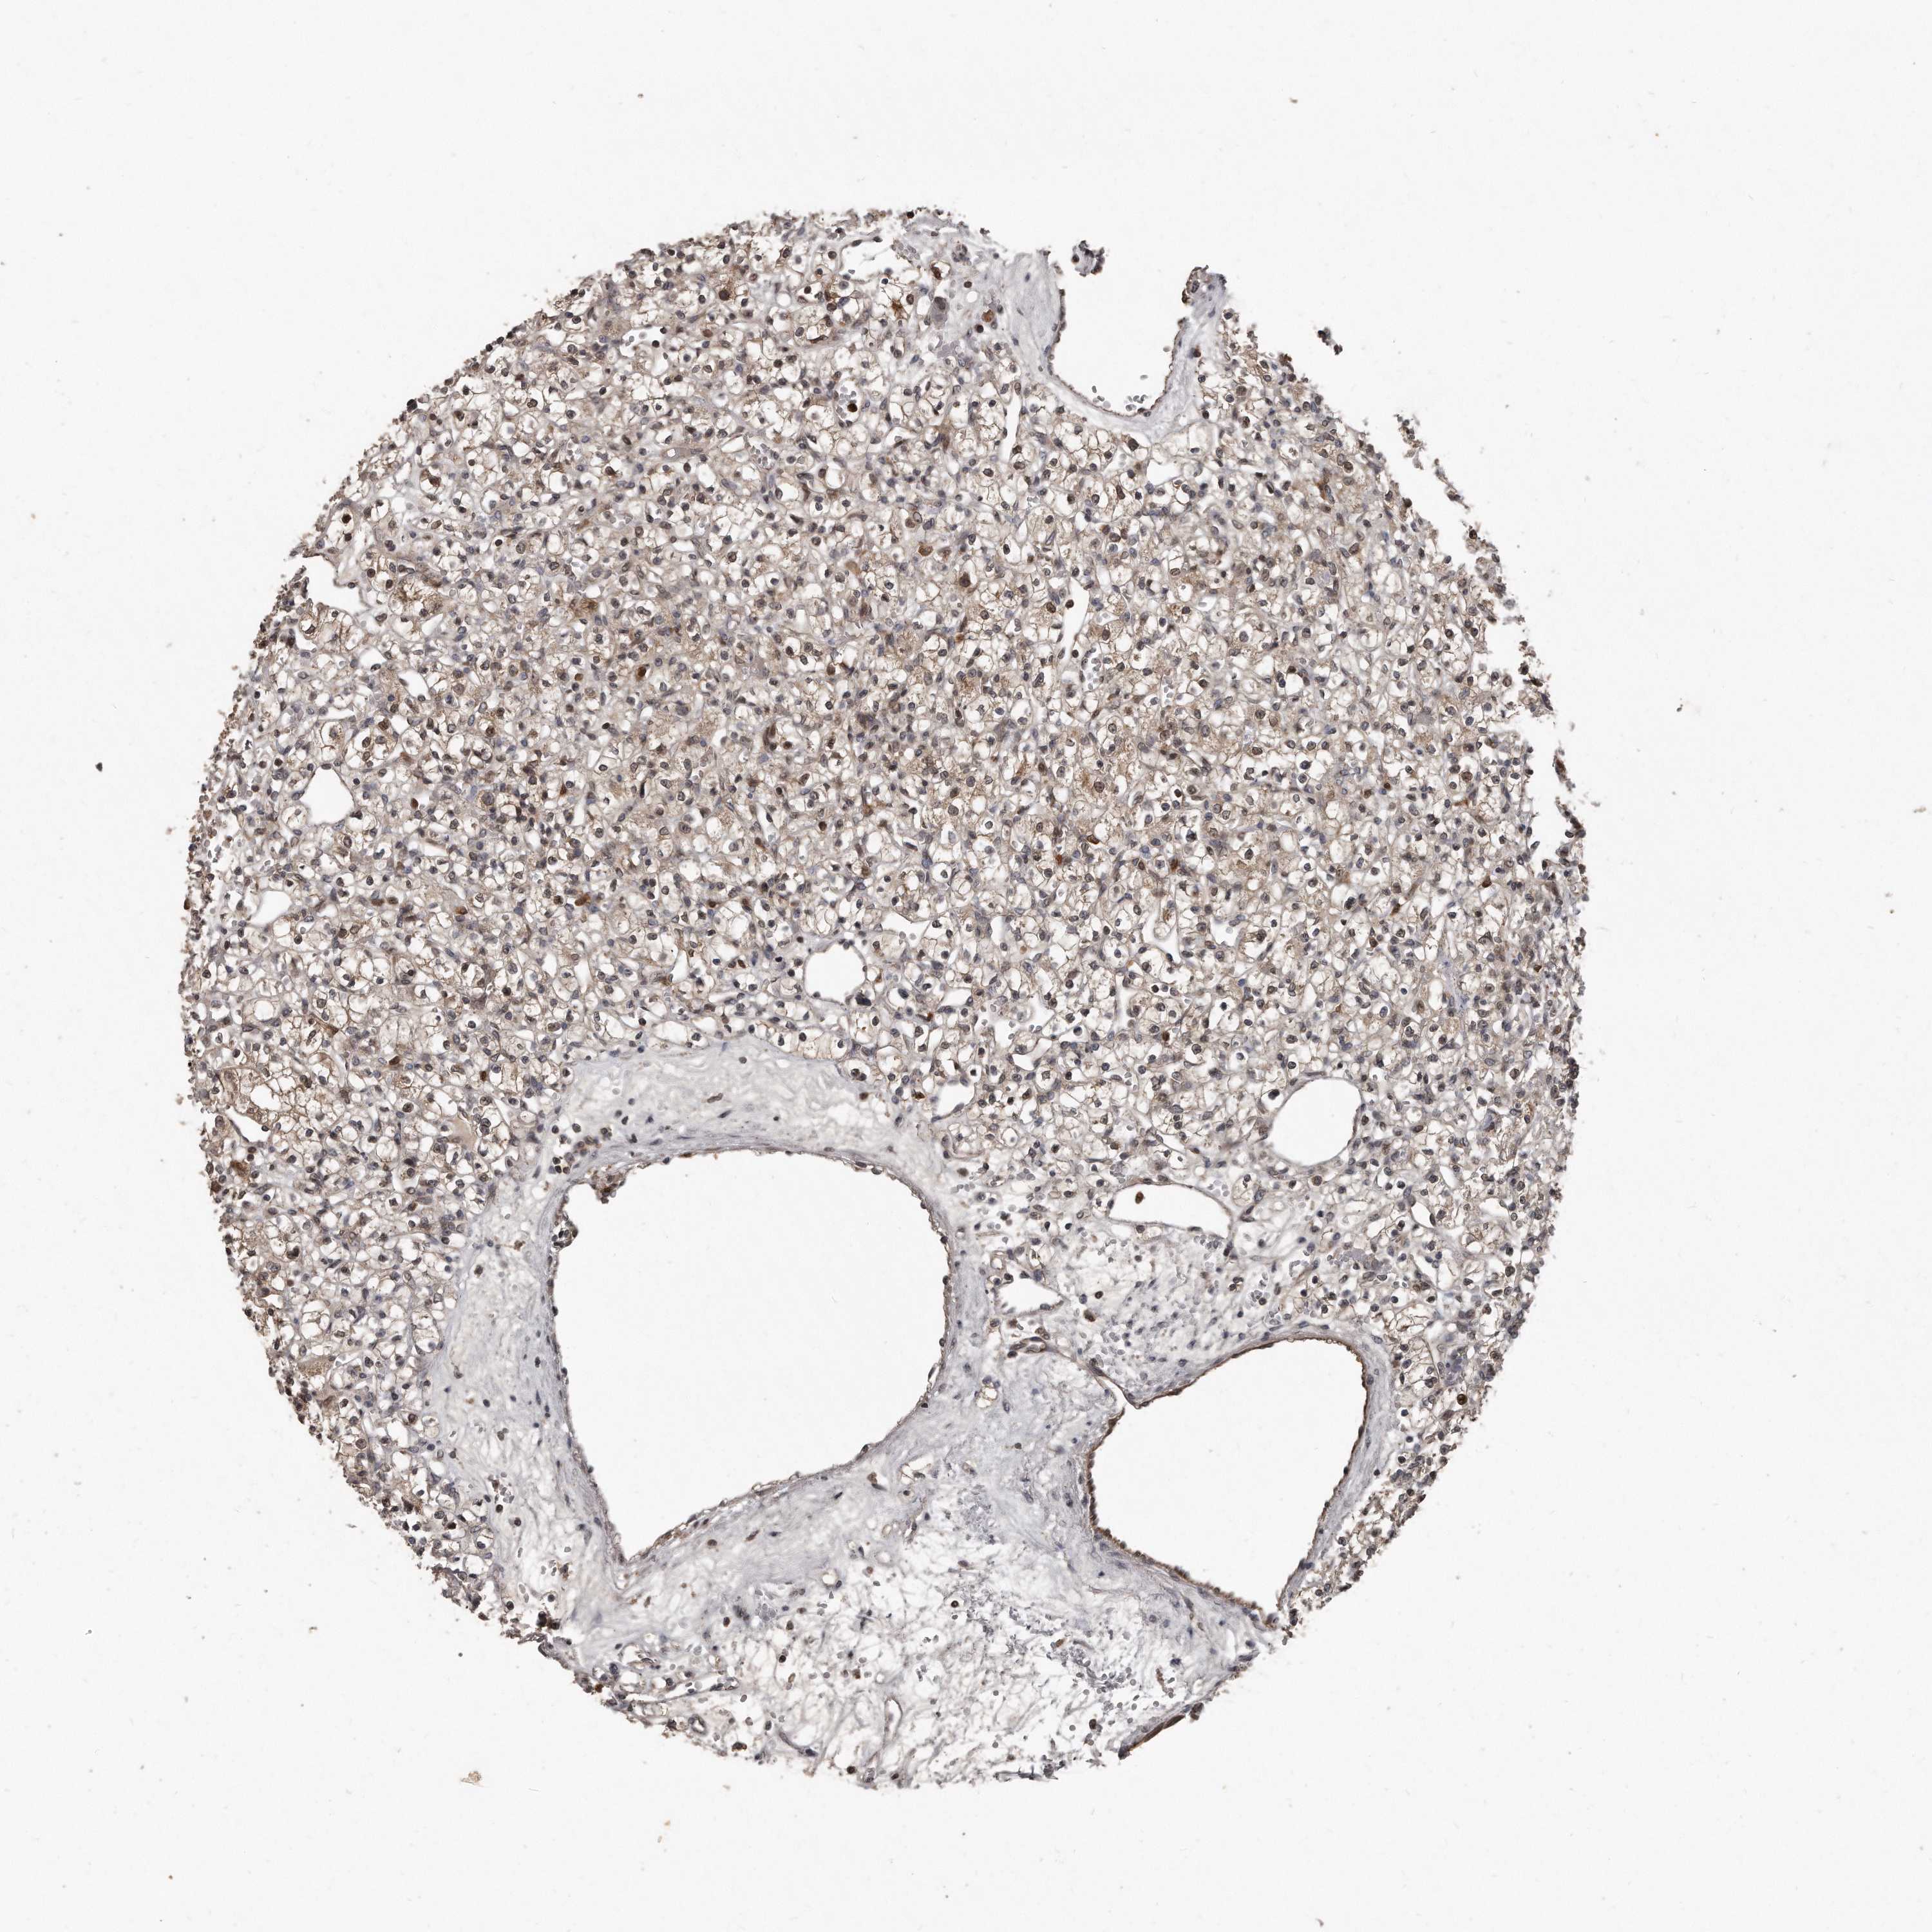

KIDNEY RENAL CLEAR CELL CARCINOMA (VALIDATION) - Interactive survival scatter ploti

The Survival Scatter plot shows the clinical status (i.e. dead or alive) for all individuals in the patient cohort, based on the same data that underlies the corresponding Kaplan-Meier plots. Patients that are alive at last time for follow-up are shown in blue and patients who have died during the study are shown in red.

The x-axis shows the expression levels (FPKM) of the investigated gene in the tumor tissue at the time of diagnosis. The y-axis shows the follow-up time after diagnosis (years). Both axes are complimented with kernel density curves demonstrating the data density over the axes. The top density plot shows the expression levels (FPKM) distribution among dead (red) and alive patients (blue). The right density plot shows the data density of the survived years of dead patients with high and low expression levels respectively, stratified using the cutoff indicated by the vertical dashed line through the Survival Scatter plot. This cutoff is automatically defined based on the FPKM cutoff that minimizes the p-score. The cutoff can be changed by dragging the vertical line or by entering a cutoff value in the square labeled "Current cut-off".

Under the Survival Scatter plot the p-score landscape (black curve; left axis) is shown together with dead median separation (red curve; right axis). Dead median separation is the difference in median mRNA expression between patients who have died with high and low expression, respectively. It is calculated as follows: median FPKM expression of dead patients with high expression - median FPKM expression of dead patients with low expression. This is intended to aid the user in visually exploring custom cutoffs and the associated p-scores and dead median separation.

Individual patient data is displayed and can be filtered by clicking on one or more of the category buttons on the top of the page. Categories describing expression level and patient information include: high, low, alive, dead, female, male and tumor stages. The scale of the x-axis can be toggled between linear and log-scale by clicking on the "x log" button. Mouse-over function shows TCGA ID, patient information and mRNA expression (FPKM) for each patient.

& Survival analysisi

Kaplan-Meier plots summarize results from analysis of correlation between mRNA expression level and patient survival. Patients were divided based on level of expression into one of the two groups "low" (under cut off) or "high" (over cut off). X-axis shows time for survival (years) and y-axis shows the probability of survival, where 1.0 corresponds to 100 percent.

GCH1 is not prognostic in Kidney Renal Clear Cell Carcinoma (validation)

Best expression cut offi

Based on the FPKM value of each gene, patients were classified into two groups and association between prognosis (survival) and gene expression (FPKM) was examined. The best expression cut-off refers the FPKM value that yields maximal difference with regard to survival between the two groups at the lowest log-rank P-value. Best expression cut-off was selected based on survival analysis .

When clicking on this number, the vertical dashed line indicating cut-off, the interactive survival plot, and the Kaplan-Meier curve will be adjusted to show results based on the best expression cut-off.

: 8.52

TCGA RNA samplesi

RNA-seq data is reported as average FPKM (number Fragments Per Kilobase of exon per Million reads), generated by the The Cancer Genome Atlas (TCGA) .

Normal distribution across the dataset is visualized with box plots, shown as median and 25th and 75th percentiles. Points are displayed as outliers if they are above or below 1.5 times the interquartile range. FPKM values of the individual samples are presented next to the box plot.

Average pTPM 5.6

Number of samples 100